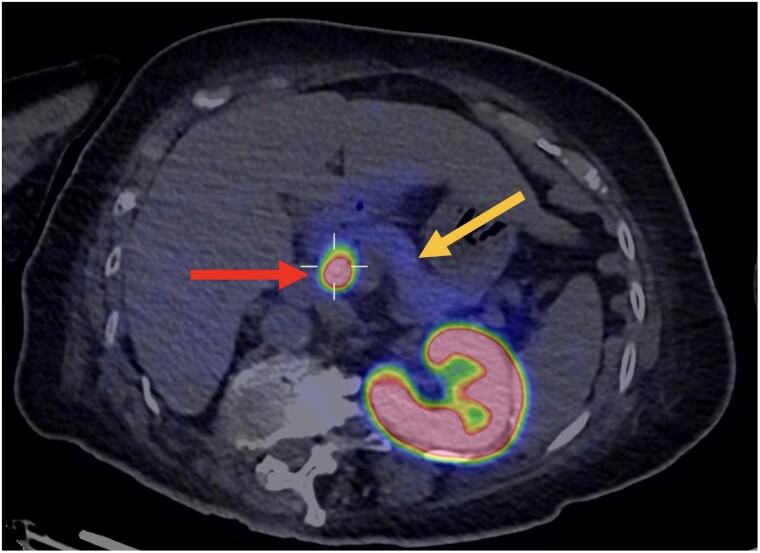

A 75-year-old female presented with fasting hypoglycemic episodes. A supervised fast ended at 72 hours fulfilling Whipple triad, with suppressed insulin and C-peptide levels, but discordantly suppressed serum β-hydroxybutyrate levels. After 21 months of recurring symptoms, a repeat fast ended at 48 hours with Whipple triad, suppressed serum β-hydroxybutyrate level, and borderline nonsuppressed C-peptide level, suggesting endogenous hyperinsulinism. Serum insulin levels were discordantly suppressed. Computed tomography (CT) of the abdomen demonstrated an enhancing 1.36 × 0.93-cm nodule in the head of the pancreas. Endoscopic ultrasound (EUS)-guided fine-needle aspirate of the lesion derived cytology consistent with a neuroendocrine tumor, but fine-needle core biopsy returned normal pancreatic tissue. Because the results were equivocal, functional imaging with 68Gallium-DOTA-exendin-4 positron emission tomography CT was performed, which confirmed the diagnosis of a single head-of-pancreas insulinoma. The patient declined surgical resection. Oral diazoxide therapy resulted in significant peripheral edema. Hence, EUS-guided radiofrequency ablation of the lesion was performed, and the patient remains symptom free 10 months postprocedure. This case illustrates that (1) exendin-4-based positron emission tomography may help one confidently diagnose and localize insulinoma when prior biochemical or endoscopic biopsy results are ambiguous; and (2) EUS-guided radiofrequency ablation is an efficacious alternative option to surgical resection in the frail, elderly patient with insulinoma.

一名75岁女性表现为空腹低血糖发作。监督禁食在72小时结束,满足惠普尔三联征,胰岛素和c肽水平受到抑制,但血清β-羟基丁酸水平受到不一致的抑制。症状复发21个月后,重复快速结束48小时,Whipple三联征,血清β-羟基丁酸水平抑制,边缘非抑制c肽水平,提示内源性高胰岛素血症。血清胰岛素水平被不一致地抑制。腹部计算机断层扫描(CT)显示胰腺头部一个1.36 × 0.93 cm的增强结节。超声内镜(EUS)引导下细针抽吸病变的细胞学表现与神经内分泌肿瘤一致,但细针核心活检显示胰腺组织正常。由于结果不明确,行68镓- dota -exendin-4正电子发射断层扫描CT功能显像,确诊为单发胰头胰岛素瘤。病人拒绝手术切除。口服二氮唑治疗导致明显的外周水肿。因此,eus引导下对病变进行射频消融,术后10个月患者仍无症状。该病例表明:(1)当先前的生化或内镜活检结果不明确时,基于exendin-4的正电子发射断层扫描可以帮助患者自信地诊断和定位胰岛素瘤;(2)超声引导下射频消融对于体弱的老年胰岛素瘤患者是手术切除的有效替代选择。